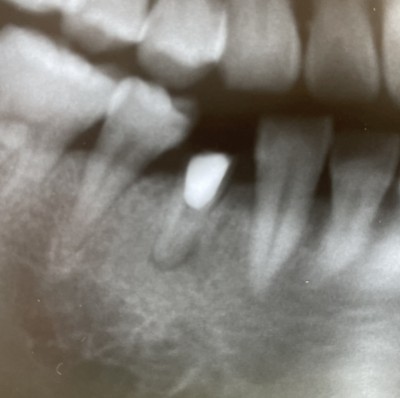

【歯内療法9年経過症例】

2020.02.06 症例紹介